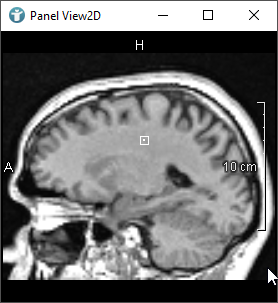

MeVisLab provides modules to create contours in images. 3D objects that encapsulate these contours are called Contour Segmentation Objects (CSOs).

In the next image, you can see a rectangular shaped CSO. The pink circles you can see are called Seed Points.

Seed Points define the shape of the CSO. In the case of a rectangle, you need four Seed Points forming the corners to define the whole rectangle.

The points forming the blue lines are called Path Points.

The Path Points form the connection between the Seed Points whereby contour objects (CSOs) are generated. CSOs are often closed, but do not need to be.

In general, the Seed Points are created interactively using an editor module and the Path Points are generated automatically by interpolation or other algorithms.